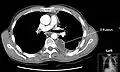

A pleural effusion appears as an area of whiteness on a standard posteroanterior chest X-ray.[12] Normally, the space between the visceral pleura and the parietal pleura cannot be seen. A pleural effusion infiltrates the space between these layers. Because the pleural effusion has a density similar to water, it can be seen on radiographs. Since the effusion has greater density than the rest of the lung, it gravitates towards the lower portions of the pleural cavity. The pleural effusion behaves according to basic fluid dynamics, conforming to the shape of pleural space, which is determined by the lung and chest wall. If the pleural space contains both air and fluid, then an air-fluid level that is horizontal will be present, instead of conforming to the lung space.[13] Chest radiographs in the lateral decubitus position (with the patient lying on the side of the pleural effusion) are more sensitive and can detect as little as 50 mL of fluid. Between 250 and 600mL of fluid must be present before upright chest X-rays can detect a pleural effusion (e.g., blunted costophrenic angles).[14]

Chest computed tomography is more accurate for diagnosis and may be obtained to better characterize the presence, size, and characteristics of a pleural effusion. Lung ultrasound, nearly as accurate as CT and more accurate than chest X-ray, is increasingly being used at the point of care to diagnose pleural effusions, with the advantage that it is a safe, dynamic, and repeatable imaging modality.[15] To increase diagnostic accuracy of detection of pleural effusion sonographically, markers such as boomerang and VIP signs can be utilized.[16]